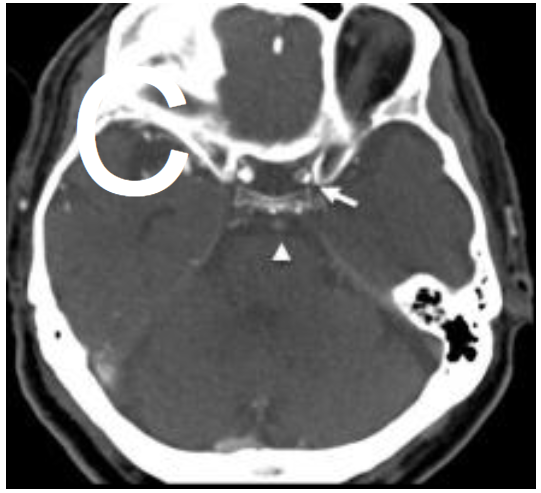

CT血管造影

(C)显示基底动脉(箭头)和左颈内动脉(箭头)同时闭塞。

VR图像显示永存舌下动脉(箭头),可以解释多区域梗死(D)。